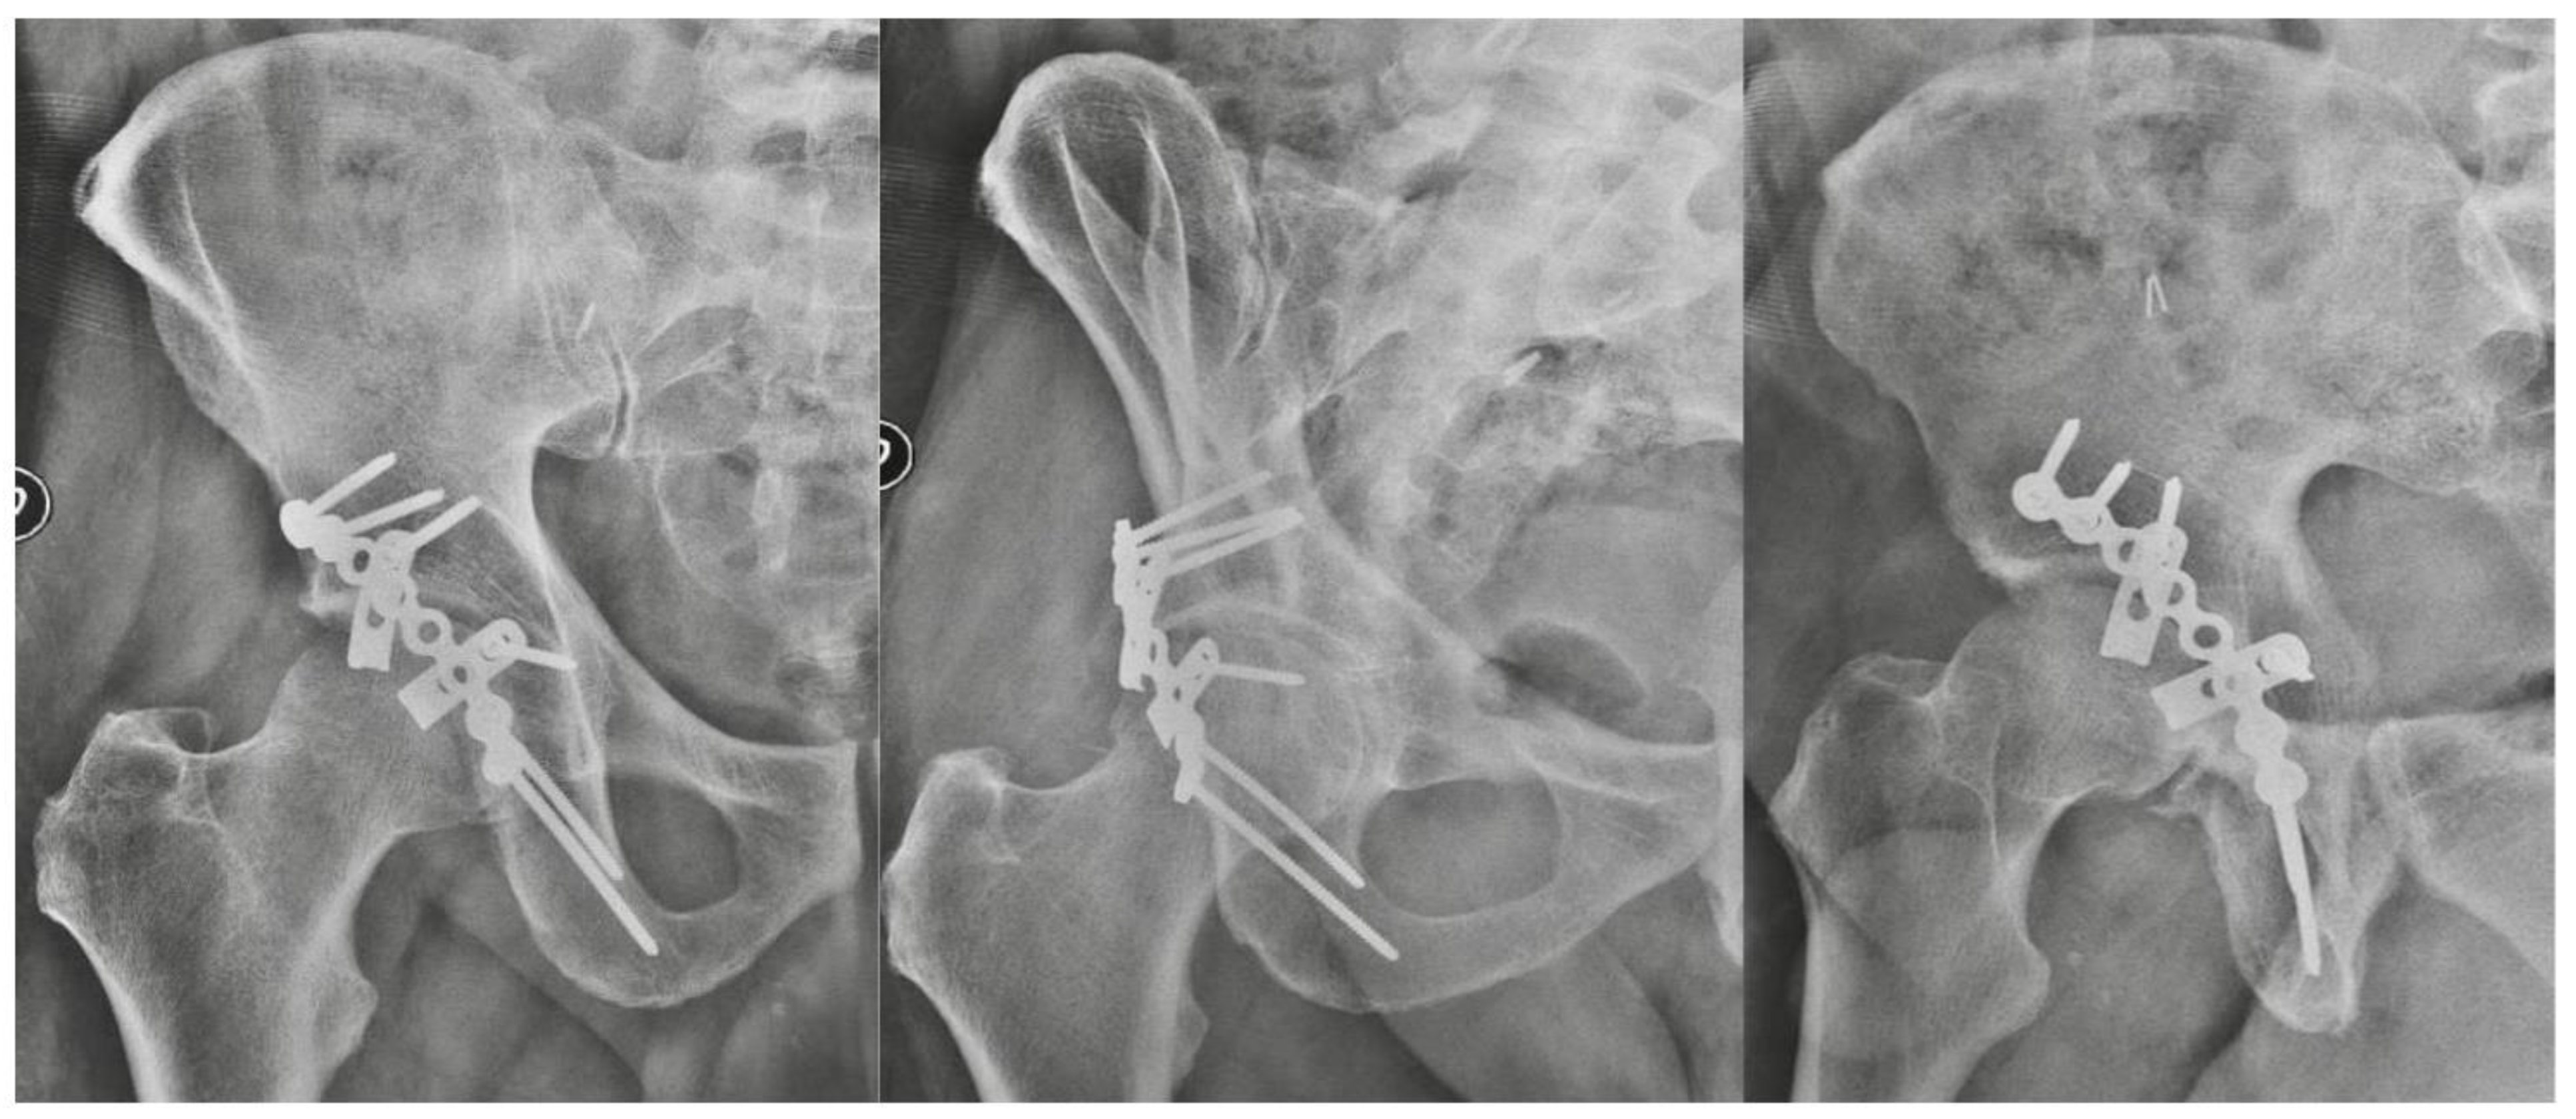

Spring Plates as a Valid Additional Fixation in Comminuted Posterior Wall Acetabular Fractures: A Retrospective Multicenter Study

2. Materials and Methods

3. Results

| Radiological outcome | Anatomical | 78.3% | 36 patients |

| Imperfect | 15.2% | 7 patients | |

| Poor | 6.5% | 3 patients | |